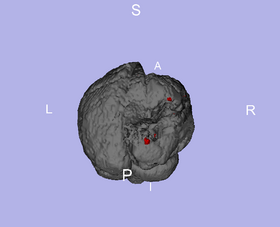

Lesion Model inside Brain

Predicted Heat Map, Manual Segmentation, Thresholded Heat Map